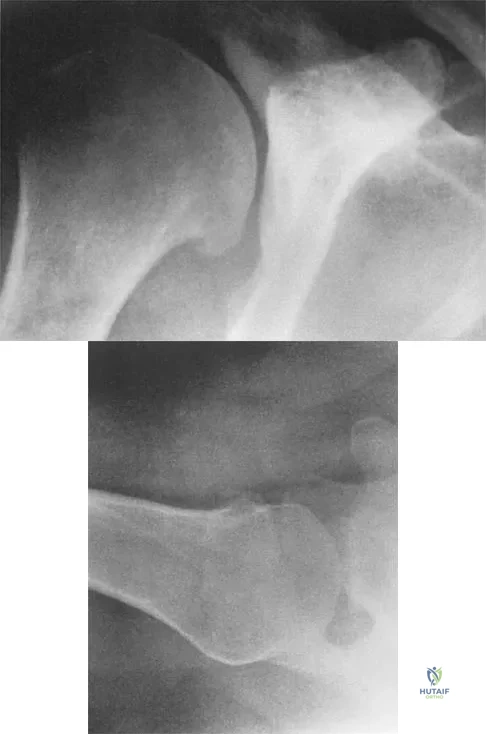

Question 10

A 51-year-old male truck driver has had progressive left hip pain for more than 2 years, and he reports that the pain has become severe in the past 9 months. He is now unable to work because of the pain. Examination reveals that range of motion of the hip is limited to 95 degrees of flexion, 0 degrees of internal rotation, and 20 degrees of external rotation. The plain radiograph, MRI scan, and intraoperative gross photographs are shown in Figures 9a through 9d. Management should consist of

Explanation